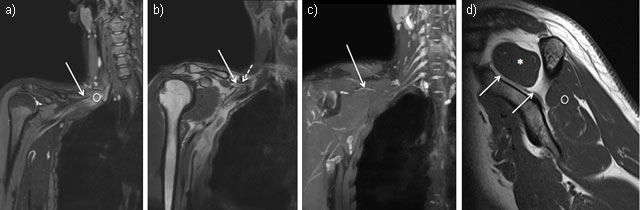

Figure 2

Coronal MR Neurography sections showing the right suprascapular nerve (solid arrow) arising from the upper trunk of the plexus brachial (circle) (2a = FIGURE 3 uploaded online manuscript) then, crossing the posterior cervical triangle in the supraclavicular fossa, deep to the omohyoid muscle (dashed arrow) (2b = FIGURE 4 uploaded online manuscript), before traveling through the suprascapular notch (2c = FIGURE 5 uploaded online manuscript). Sagittal MRI T1-weighted sequence shows the nerve inside the supraspinatus fossa where it provides motor innervation to the supraspinatus muscle (star) followed by infraspinatus muscle (circle) (2d = FIGURE 6 uploaded online manuscript).